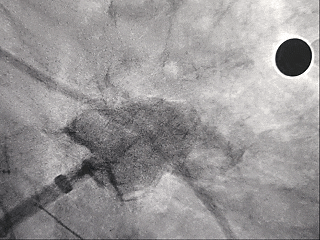

释放LAFDQ-26封堵器

封堵器展开后造影

牵拉试验:封堵器拉出心耳

封堵器牵拉未回弹

牵拉后造影,封堵器移位

上缘未挂住梳状肌,下缘露肩,导致牵拉不稳定,全回收封堵器并更换使用LAFDQ-29封堵器。